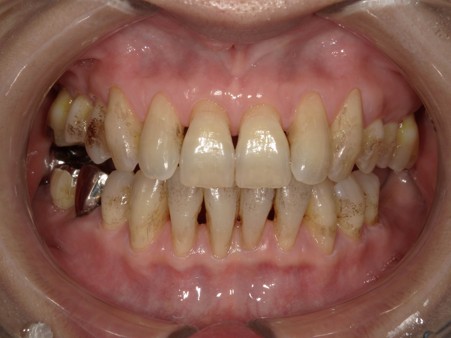

治療後

| 術後の経過・現在の様子 | ホワイトニング後は、黄色味が抜けて全体的に統一感のある状態に仕上がったと思います。 ステイン除去後、口腔内への意識変化からホワイトニングまで行いました。 長年気になってはいたけど、そのままにしていたステインと歯の色だったそうです。ホワイトニング終了後の仕上がりには大変満足されていました。 今後は出来るだけ今の状態をキープしていきたいとの事で、着色予防のために始めに行っていたパウダーを使ったメンテナンスを継続していきます。 今後も患者さんの理想の口腔内を保てるようにサポートしていきます。 |